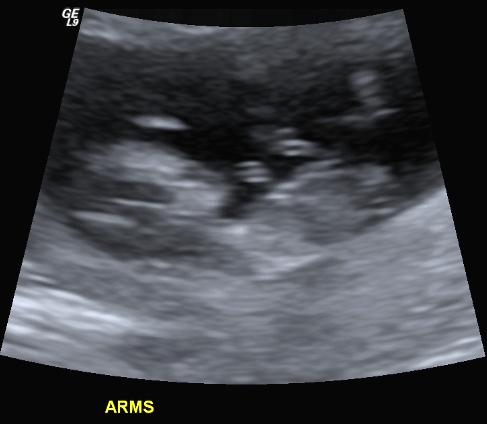

I finally managed to get hold of my u/s disc and have selected a few of the pics I think could have a nub in them (I'm still pretty hopeless at working out nubs).

There is only 1 pic from my 19 week scan that even comes remotely close to the bottom region and I'm pretty sure it is not a potty shot, just of legs from above I think??? (second last pic...biggest one)...I'm a little p'd off with the tech as I asked him to get a pic for me and he obviously didn't.

I have included quite a few from my early scan but bub was 11w4d so I understand prob slightly early still.